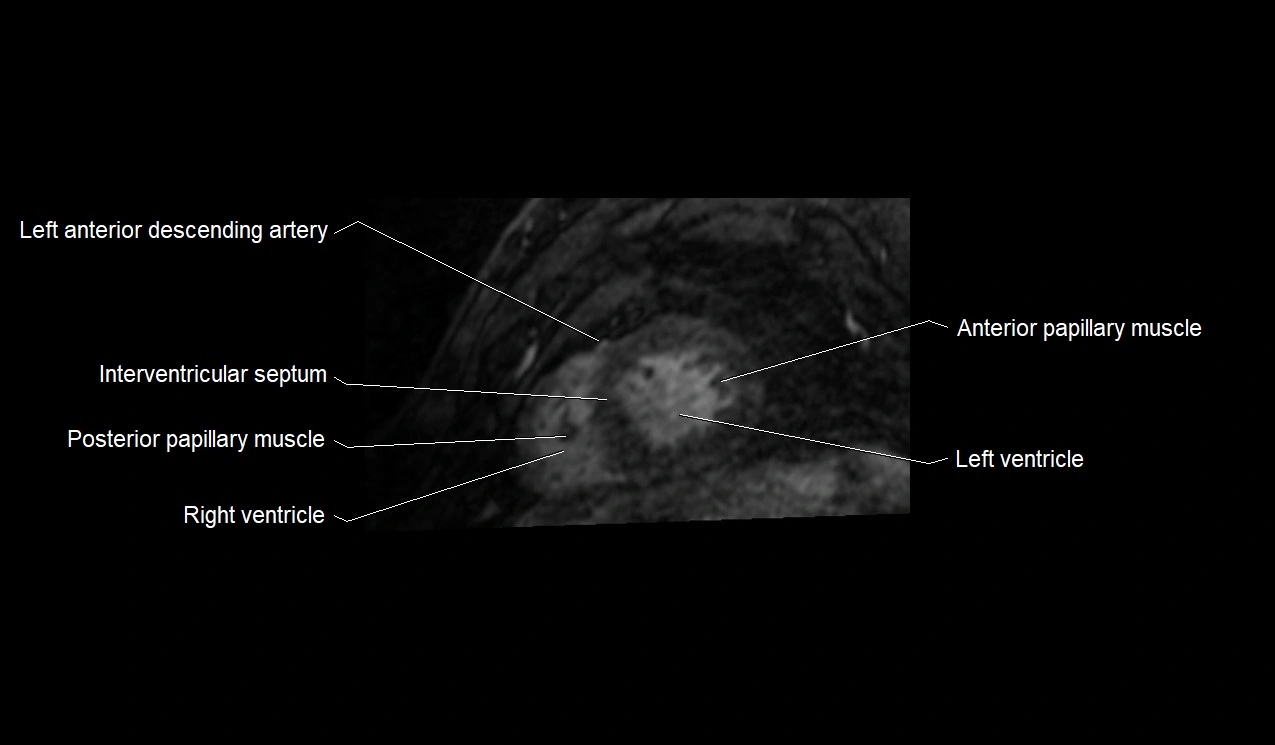

MRI image